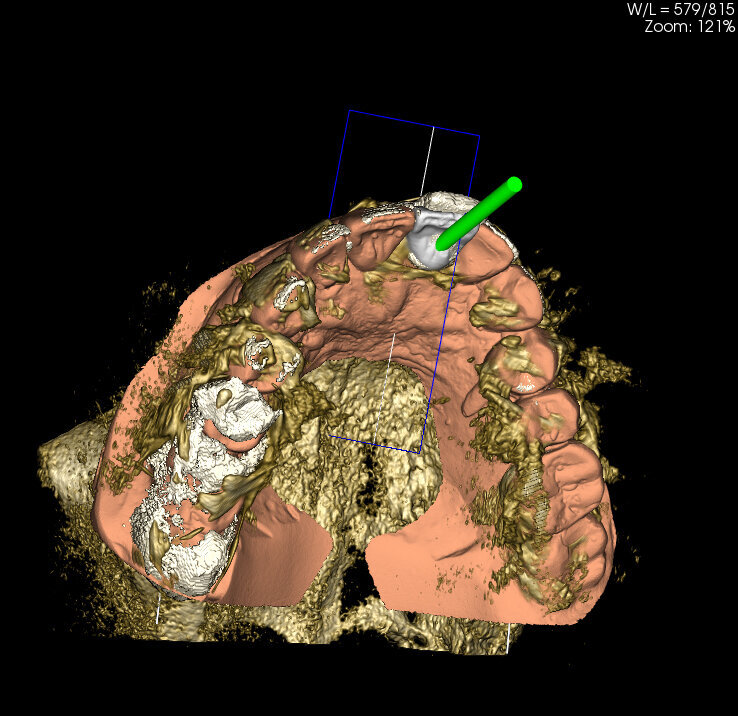

The intraoral scan is imported into CAD software and transformed into a virtual master model without the tooth to be extracted and a separate STL shape of the ideal CAD-designed tooth (Fig. 9). Now there is the opportunity for 3D evaluation of the dimensional relation between the new tooth and the soft tissue before extraction. In the current case, the tooth involved had not been extracted and a CBCT scan was performed (X-Mind trium, ACTEON; 110 x 80 mm field of view; 0.15 mm voxel size) for further investigation and treatment planning. In the AIS 3D App software that comes with the CBCT X-Mind trium device, STL files can be matched and aligned with the 3D bone volume, thus giving the opportunity to plan the future implant position taking into account the shape and position of the future crown (Figs. 10a & b). In accordance with the prosthetic procedure preferred, cemented versus screw-retained, CAD/CAM-fabricated versus manual layering and the type of material to be used, all the information for the final treatment plan is available, on which decisions can be made regarding GBR, connective tissue graft and timing of implant loading.

It became evident that the short-rooted tooth could be extracted without compromising the buccal bone, and that there was sufficient bone volume and quality to obtain good primary stability of the implant. Thanks to the AIS 3D App software, this information can be visualised using the bone density tool and linear measures tool (Fig. 10c) and represented in a graphic or according to a coloured scale. The presence of the nasopalatine duct prohibited ideal palatal positioning of the implant, and if the implant were to be placed flush with the palatal alveolar bone, this would have resulted in a 1.5–2.0 mm high exposure of the implant collar on the buccal aspect (Fig. 11b). This information, combined with the aesthetic analysis, led to the decision to place the implant in that position and to augment the buccal bone volume with a contemporaneous GBR procedure, thus also providing for major soft tissue support. As often described in the literature, it is to be expected that in some measure the implant will deviate buccally2–4 from the original planning because of the major mechanical resistance of the palatal plate. The author’s team prefers whenever possible screw-retained solutions. Several production centres are capable of milling angulated screw access holes in cobalt-chromium abutments of up to 25°,5 which is a range that covers most cases in daily practice. It can be easily checked in the implant planning software whether the future access hole will exit on the palatal aspect of the tooth, either by angulating the implant extension tool or by choosing a virtual abutment from the library. Confirming being in the safety range from this point of view allowed for an approach that foresaw the implant in native bone without the necessity for major GBR on the apical aspect of the implant. Knowing that a flap needed to be raised to facilitate the marginal tissue augmentation, it was decided to use a surgical guide (Figs. 11c) for only the first drill to determine with precision the position and angulation of the osteotomy that would be performed freehand thereafter. In order to limit surgery time and eliminate unpredictable factors inherent in immediate loading, a removable temporary prosthetic tooth was produced in advance.

Innovative technologies enable extremely accurate diagnosis and treatment planning. Affordable high-quality CBCT has profoundly changed our profession. In the current case, the detailed X-Mind trium 3D images allowed for planning and performing implant placement in the optimal mesiodistal position. Correct distances to the lateral incisor and the nasopalatine duct were obtained. Final choices will always remain related to the experience, skills and equipment of the performing team. After collecting all of the necessary information and knowing what technology can provide, it is possible that one team will opt for GBR and monolithic crowns, where another might try to minimise the invasiveness of surgery and employ innovative milling strategies to deliver a predictable, beautiful solution. In the actual challenging buccopalatal dimension, the implant was perfectly planned and guided into to the centre of the native bone. Guided bone regeneration was limited to the minimum and minor buccal exposure of the implant was predicted. Reviewing the case described above, the fact that bone volume could be matched with the dental preoperative situation and the CAD virtual wax-up made the whole procedure, from extraction to final restoration, highly predictable. Bone volume, bone quality, extent of GBR indicated and the type of prosthodontic solution were all known before starting treatment thanks to the implant planning with the AIS 3D App software.